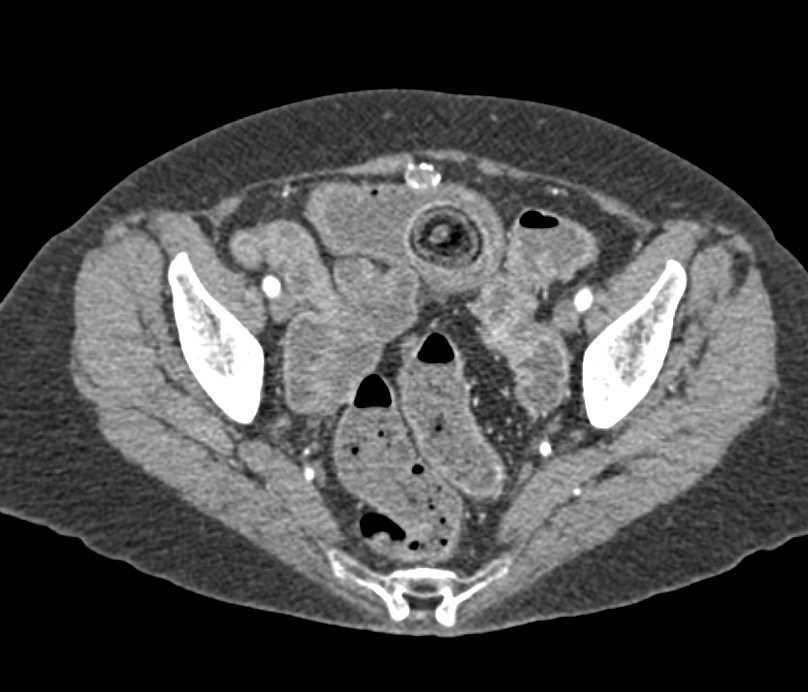

Carcinoid Tumor Root of Mesentery with Desmoplastic Reaction and Liver Metastases